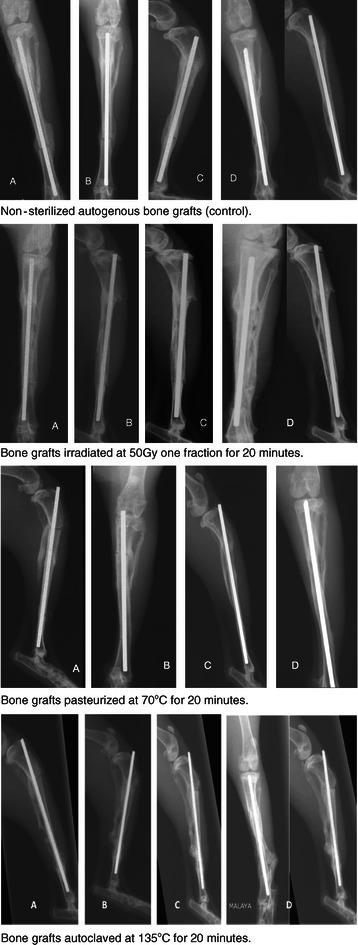

Fresh rabbit cortical bone is harvested from the tibial diaphysis and sterilized extracorporeally by pasteurization (n = 6), autoclaving (n = 6), irradiation (n = 6) and normal saline as control group (n = 6). The cortical bones were immediately reimplanted after the sterilization process. The subsequent process of graft incorporation was examined over a period of 12 weeks by serial radiographs, biomechanical and histopathological evaluations. Statistical analysis (ANOVA) was performed on these results. Significance level (α) and power (β) were set to 0.05 and 0.90, respectively.

Radiographic analysis showed that irradiation group has higher score in bony union compared to other sterilization groups (p = 0.041). ANOVA analysis of 'failure stress', 'modulus' and 'strain to failure' demonstrated no significant differences (p = 0.389) between treated and untreated specimens under mechanical loading. In macroscopic histopathological analysis, the irradiated group has the highest percentage of bony union (91.7 percent). However in microscopic analysis of union, the pasteurization group has significantly higher score (p = 0.041) in callus formation, osteocytes percentage and bone marrow cellularity at the end of the study indicating good union potential.

This experimental study shown that both irradiation and pasteurization techniques have more favourable outcome in terms of bony union based on radiographic and histopathological evaluations. Autoclaving has the worst outcome. These results indicate that extracorporeal irradiation or pasteurization of bone autografts, are viable option for recycling bone autografts. However, pasteurization has the best overall outcomes because of its osteocytes preservation and bone marrow cellularity.